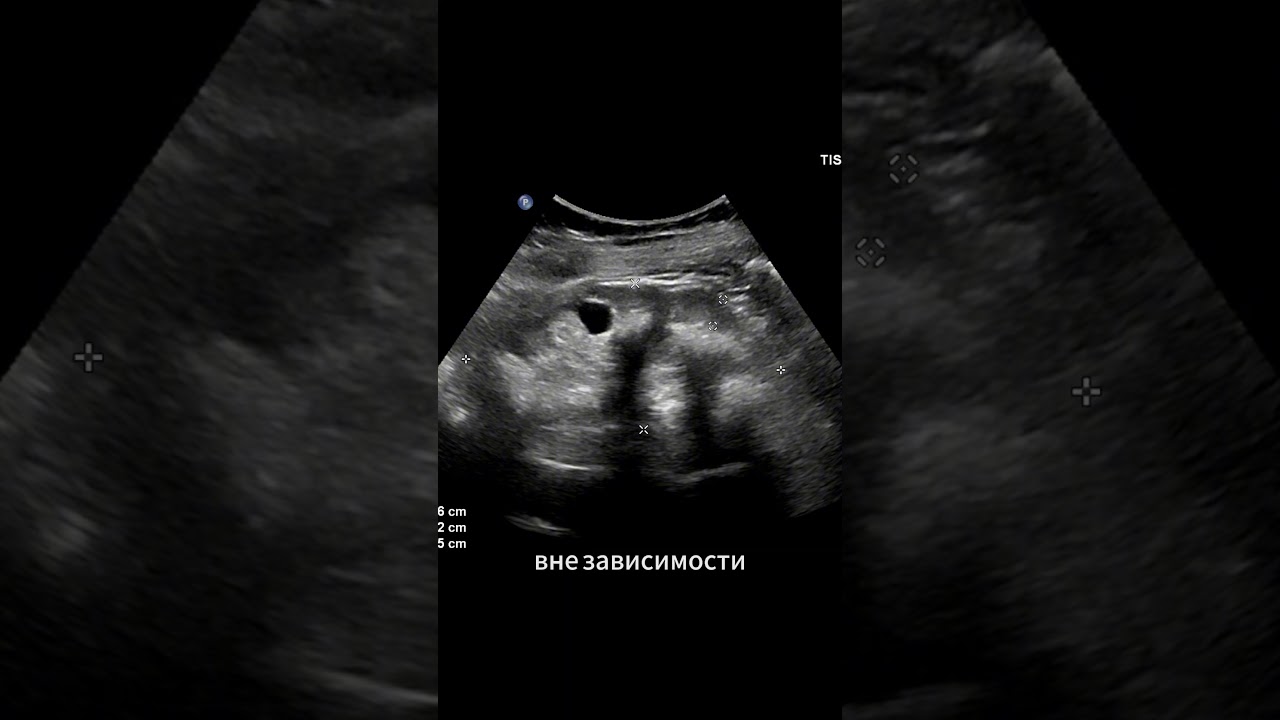

Диагностика с помощью визуализации: Для диагностики медуллярного нефрокальциноза часто используются методы визуализации, такие как ультразвуковое исследование или компьютерная томография. На этих изображениях можно увидеть характерные отложения кальция в почках, что помогает врачам в постановке диагноза.

Ультразвуковое исследование. Наблюдается увеличение эхогенности коркового слоя почки. В некоторых случаях кортикальные эхогенные структуры могут создавать акустическую тень.

- ультразвуковая диагностика почки;

Рентгенологическое исследование позволяет визуализировать кальцификаты из-за их структуры (похожа на кость), что делает их ярко отличимыми на фоне паренхимы почки. Для более детального обследования используют КТ или МРТ. Использование УЗИ не всегда эффективно. Кисты и камни могут быть визуализированы в правой, левой или обеих почках. Гиперэхогенные образования маленьких размеров часто остаются незамеченными. Этот метод дает возможность увидеть другие патологии органа. Если эти методы не позволяют определиться с окончательным диагнозом, проводится биопсия почечных тканей. Дифференциальную диагностику проводят с медуллярной губчатой почкой, гиперпаратиреозом, острым некрозом.